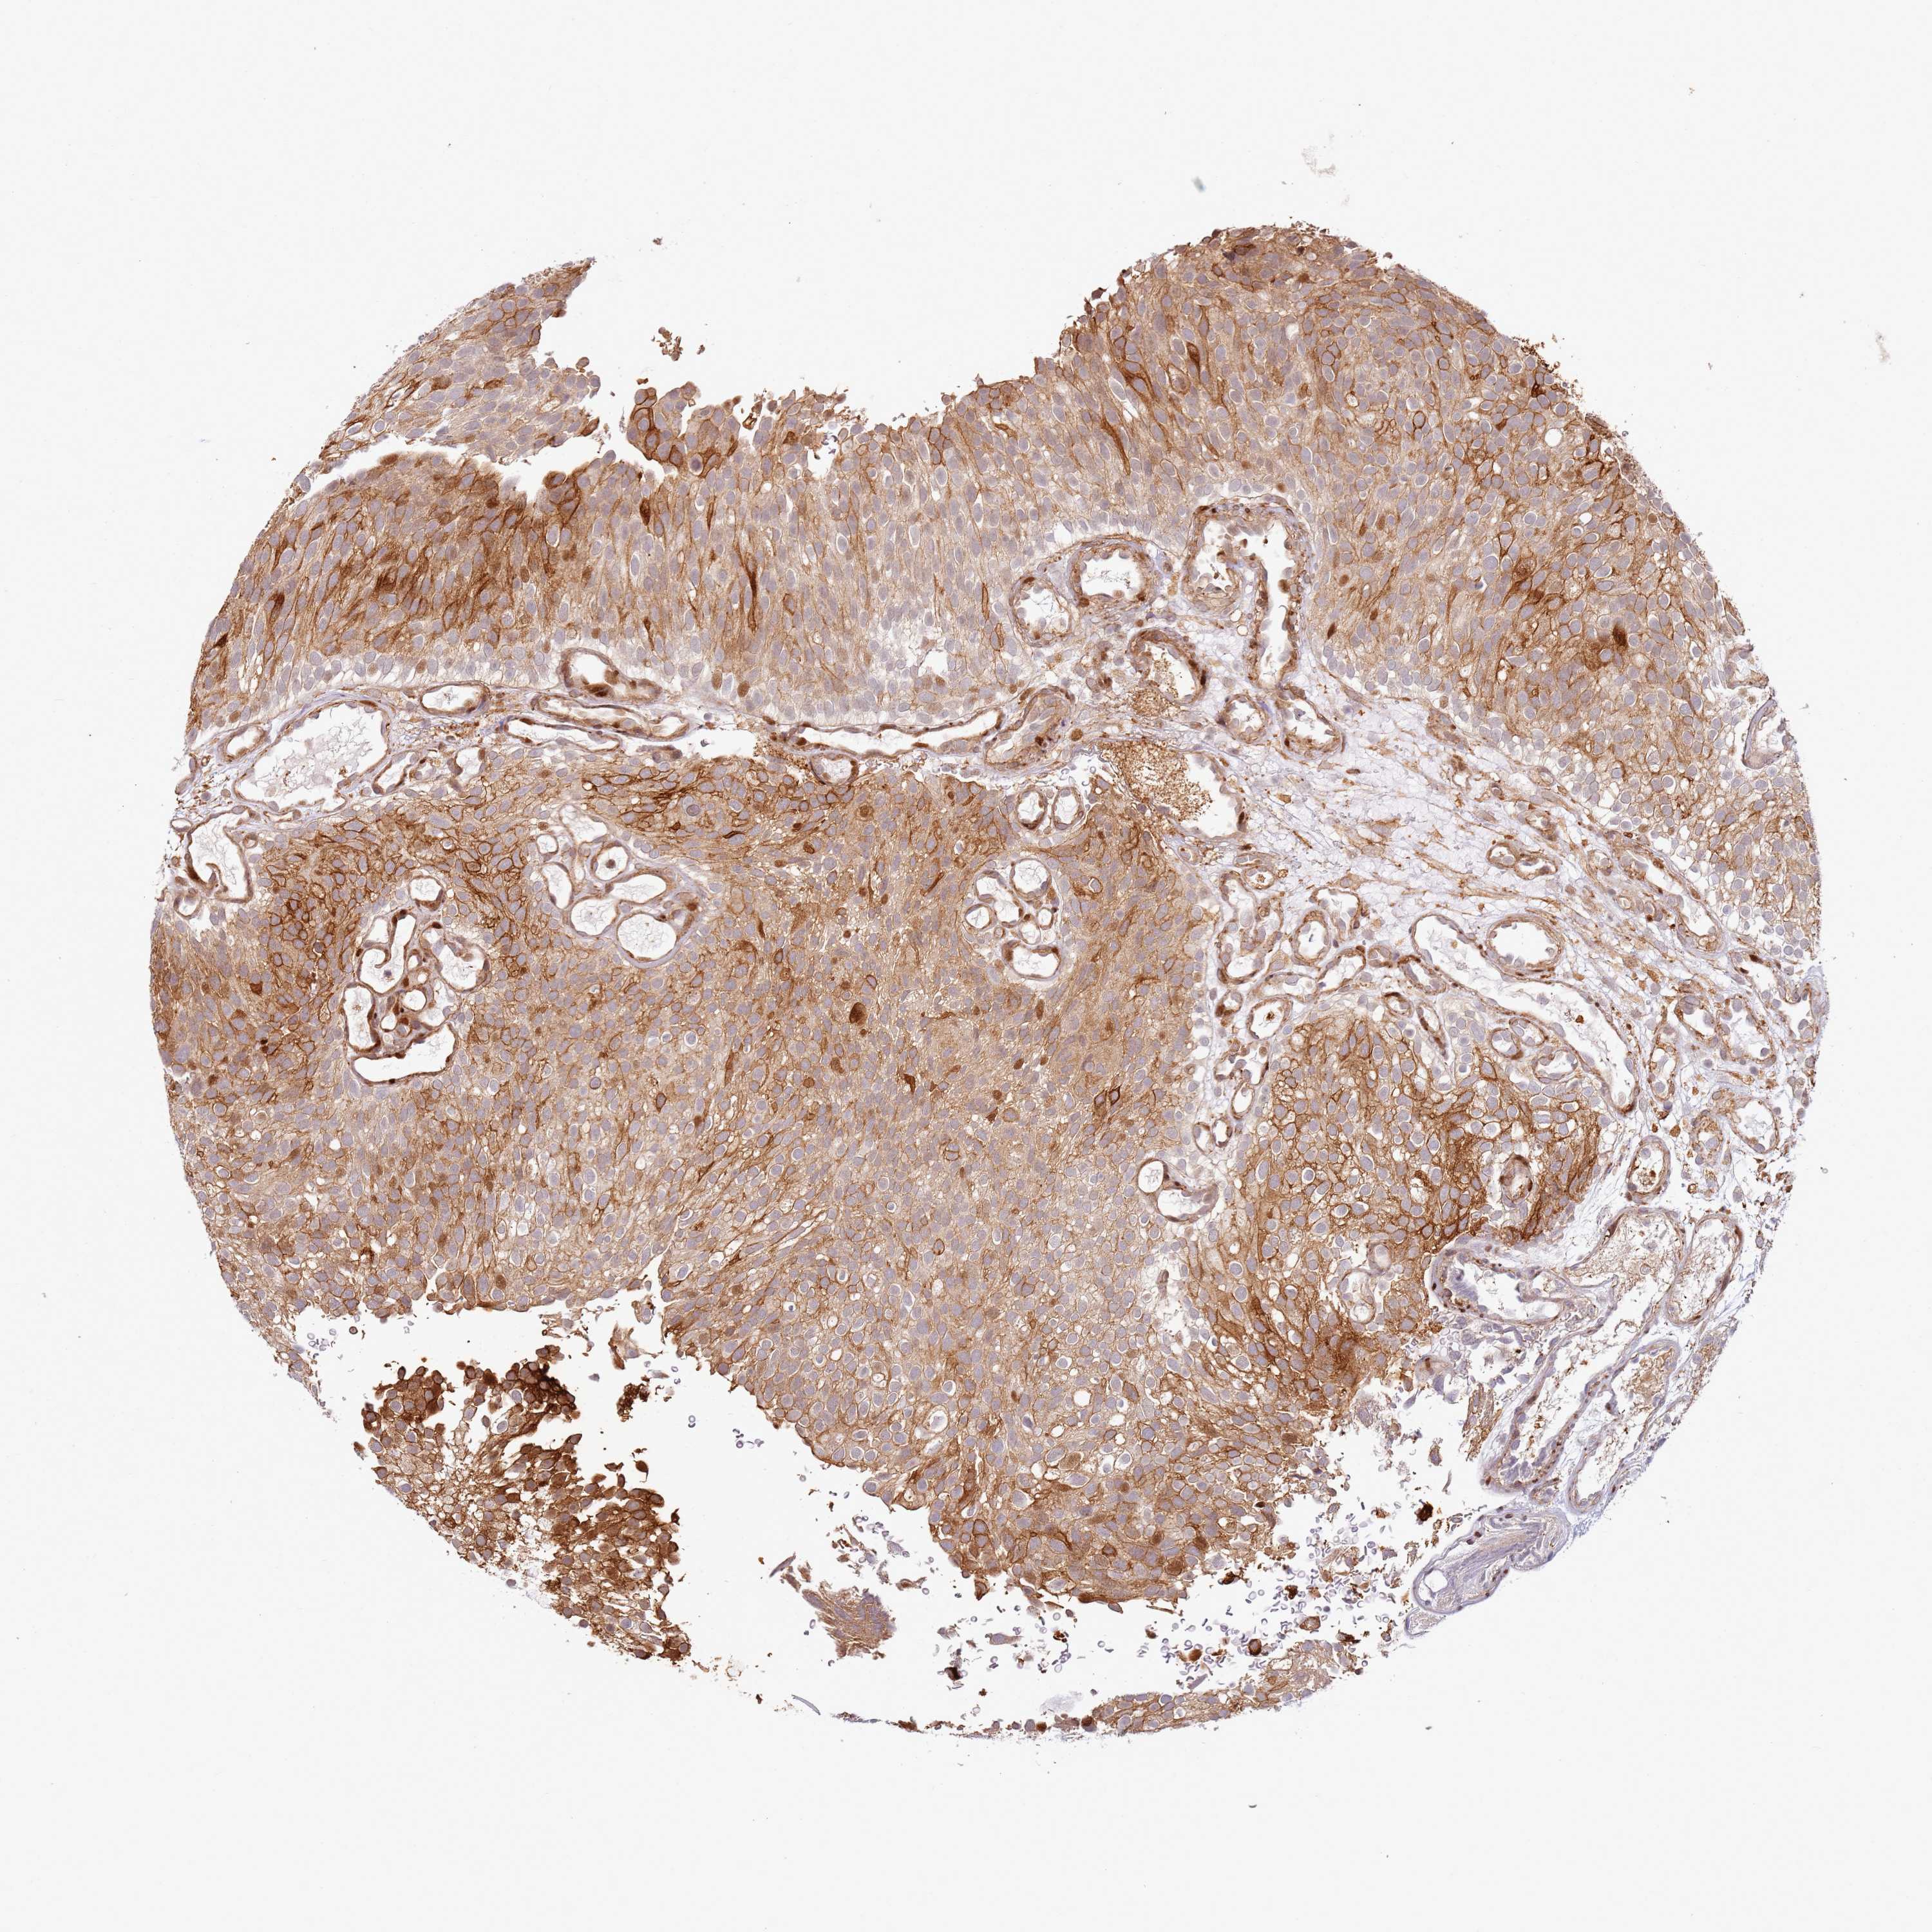

UROTHELIAL CANCER - Protein expressioni

A mouse-over function shows sample information and annotation data. Click on an image to view it in a full screen mode. Samples can be filtered based on level of antibody staining by selecting one or several of the following categories: high, medium, low and not detected. The assay and annotation is described here.

Note that samples used for immunohistochemistry by the Human Protein Atlas do not correspond to samples in the TCGA dataset.

Antibody stainingi

Antibody staining in the annotated cell types in the current human tissue is reported as not detected, low, medium, or high, based on conventional immunohistochemistry profiling in selected tissues. This score is based on the combination of the staining intensity and fraction of stained cells.

Each image is clickable and will lead to virtual microscopy that enables deeper exploration of all samples and also displays staining intensity scores, fraction scores and subcellular localization as well as patient and tissue information for each sample.

Antibody HPA047506

Staining

High

Medium

Low

Not detected

Intensity

Strong

Moderate

Weak

Negative

Quantity

>75%

75%-25%

<25%

None

Location

Nuclear

Cytoplasmic/membranous

Cytoplasmic/membranous,nuclear

Urothelial carcinoma, High grade

Urothelial carcinoma, Low grade